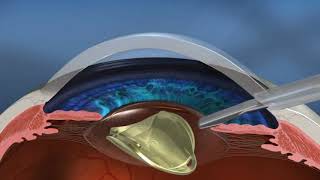

The LensX Laser Procedure (Cataract Surgery) video

LenSx Laser Cataract Surgery Video The LensX Laser Procedure (Cataract Surgery)

The LensX Laser Procedure (Cataract Surgery) Laser-Assisted Cataract Surgery (LenSx) with Dr. Grover Robinson IV